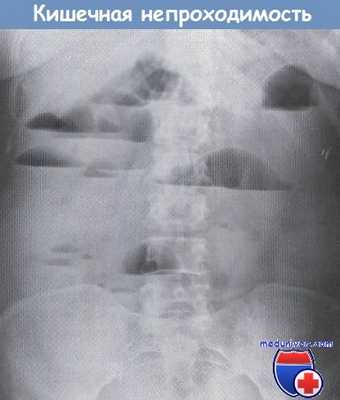

Уровни газа и жидкости при кишечной непроходимости.

• Уровни жидкости и растяжение толстой кишки: соответствуют уровню обструкции; «переходная точка» соответствует уровню механической обструкции: наличие воздуха, определяемого в прямой кишке, подозрительно в отношении псевдообструкции или энтерита.

• Дилатация толстой кишки с симптомом «кофейного зерна»: заворот сигмовидной кишки (ось направлена к ЛВК) или слепой кишки (ось направлена к ПНК).

• Диффузное расширение толстой кишки: максимально до 6 см (1,5 позвонка) для поперечно-ободочной кишки, 12 см - для слепой. Критический диаметр зависит от скорости развивающейся дилатации.